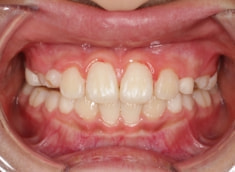

治療前

治療後(1年7ヶ月後)

治療開始から6ヶ月で反対咬合の解消は達成されておりますが、これで治ったわけではなく、上顎の劣成長を改善しなければならないので、ここからしっかりとフェイスマスクを使用していただきます。